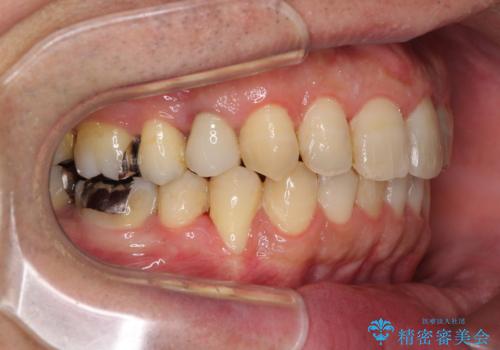

- 外に飛び出した側方の歯と、前歯のデコボコを気にして来院された患者様です。

IPR(歯と歯の間を削る)によってデコボコが解消するように設計し、インビザラインにより治療を行うこととしました。

治療途中で1年半以上通院されない時期があったため、後戻りが生じたことで治療期間が長くなってしまいました。

親知らずを抜去したことで、下顎のデコボコがきれいに解消されました。